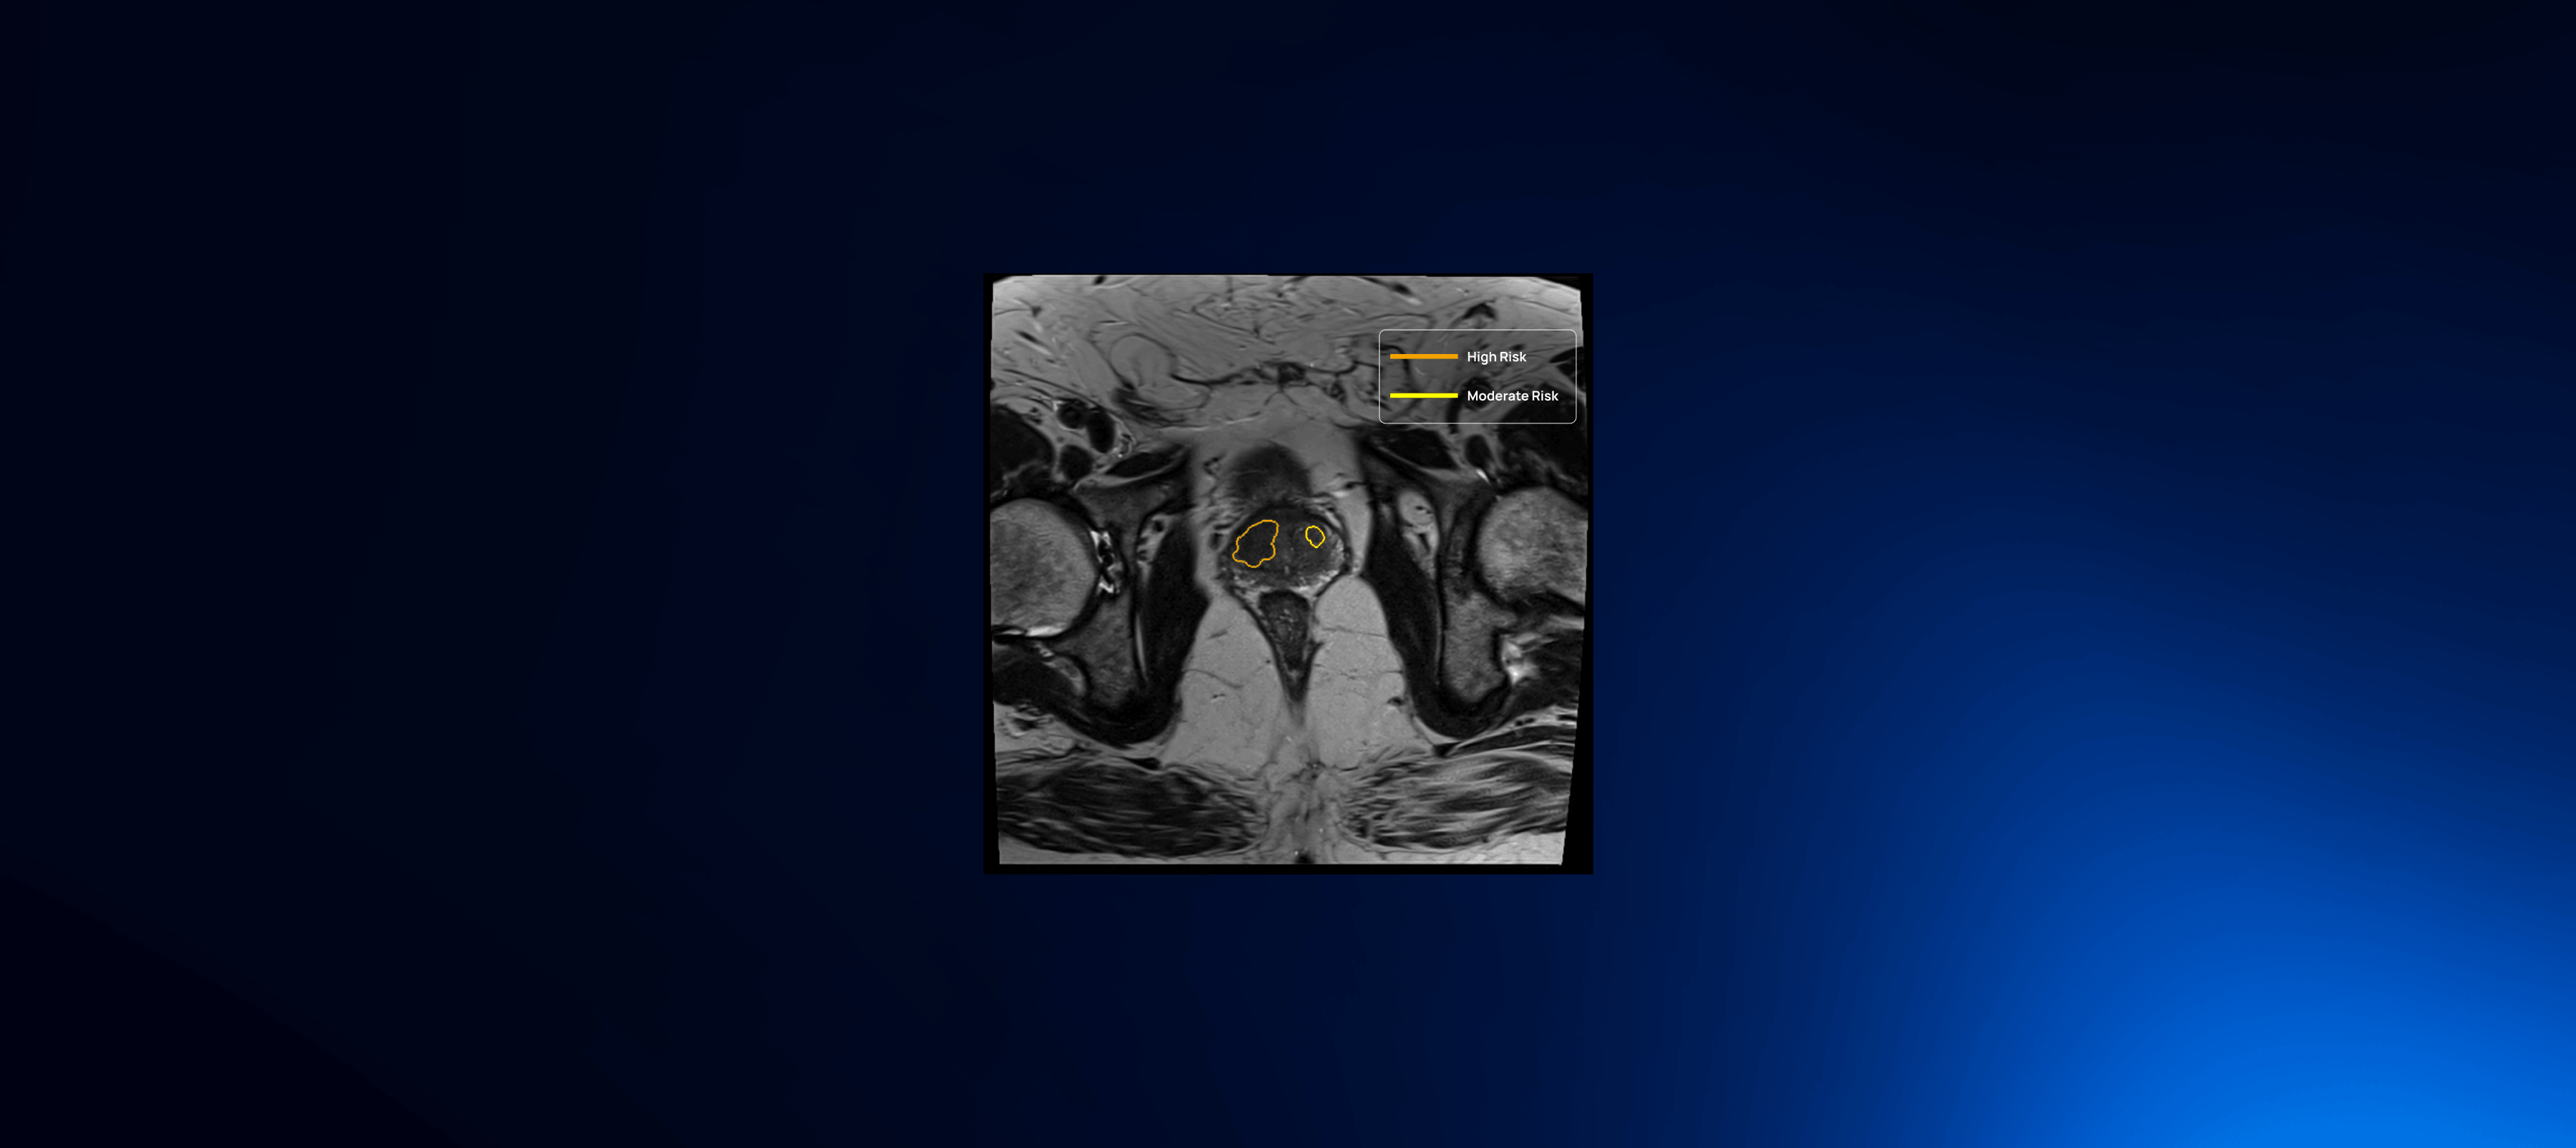

Aggressive cancer detection and diagnosis

QP-Prostate is setting a new standard for accuracy, speed, and diagnostic precision. Its AI algorithm identifies and stratifies by likelihood intermediate and high-grade aggressive prostate cancer lesions, and provides a segmentation of the prostate. This allows Health Care Professionals to improve their diagnostic accuracy and fusion biopsy planning.

Lesion detection & diagnosis

QP-Prostate automatically identifies and highlights prostate regions suspicious for aggressive prostate cancer, assigning each a confidence-based classification score.